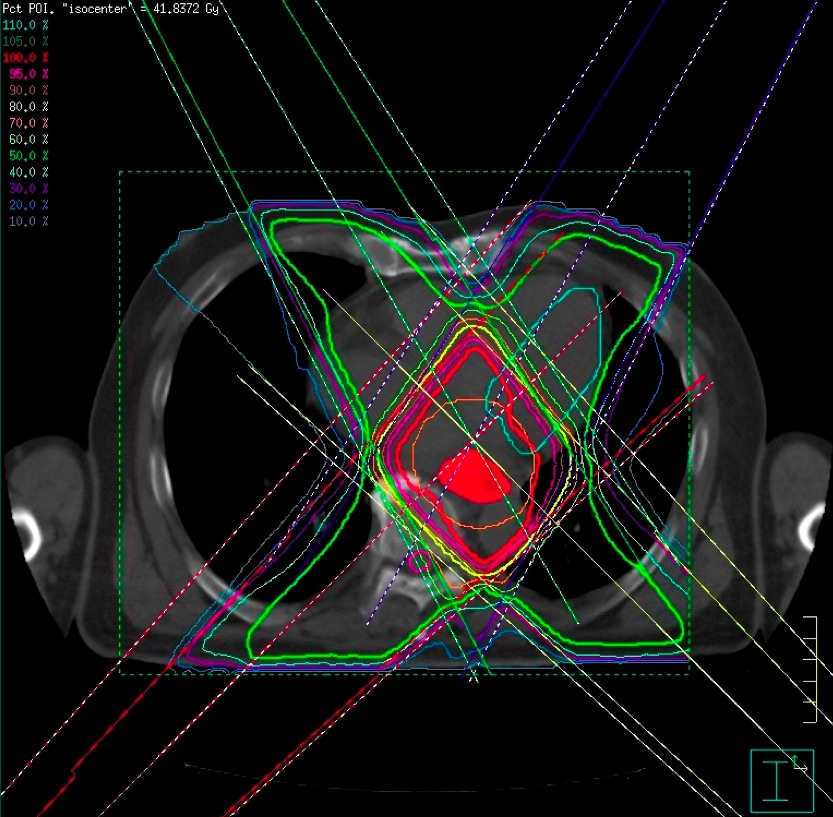

まず申し上げたいのは、最近の放射線治療は「がん」治療のかなでも副作用の少ない治療法とされています。それには多くの技術革新があっての結果ですが、一般にピンスポイント照射とも呼ばれている高精度な三次元治療計画が最も重要な役割を果たしています。それは副作用のでやすい臓器を避けて病巣に放射線を集中照射する技術です。写真4をご覧ください。

赤い肺癌に放射線照射を行うときに最も注意しなければならないのは緑の脊髄です。画像情報を駆使して、脊髄障害を起こさずに肺癌病巣に照射する方法を事前に十分検討してから、最も良い方法を選んで実際の治療を行うのです。写真5は主に食道に放射線を集中しものですが、ここでは前後にある心臓と脊髄を避けて4方向から照射しています。この方法で癌病巣や脊髄・心臓にどの位の放射線があたるのかを写真6のようなグラフを描いて評価します。したがって、昔のコバルト治療時代の副作用とは比較にならないほど軽く済むことが多くなりました。それでも副作用には個人差があり、特に治療中に発生する早期反応は化学療法でも強まり、ある程度は我慢しなければならない場合もあるでしょう。さらに副作用に対応する腫瘍看護学も進歩しており、日常のケアが行き届くようになっていますので、何か辛いことがあれば医療スタッフに遠慮なく相談したほうがよいでしょう。